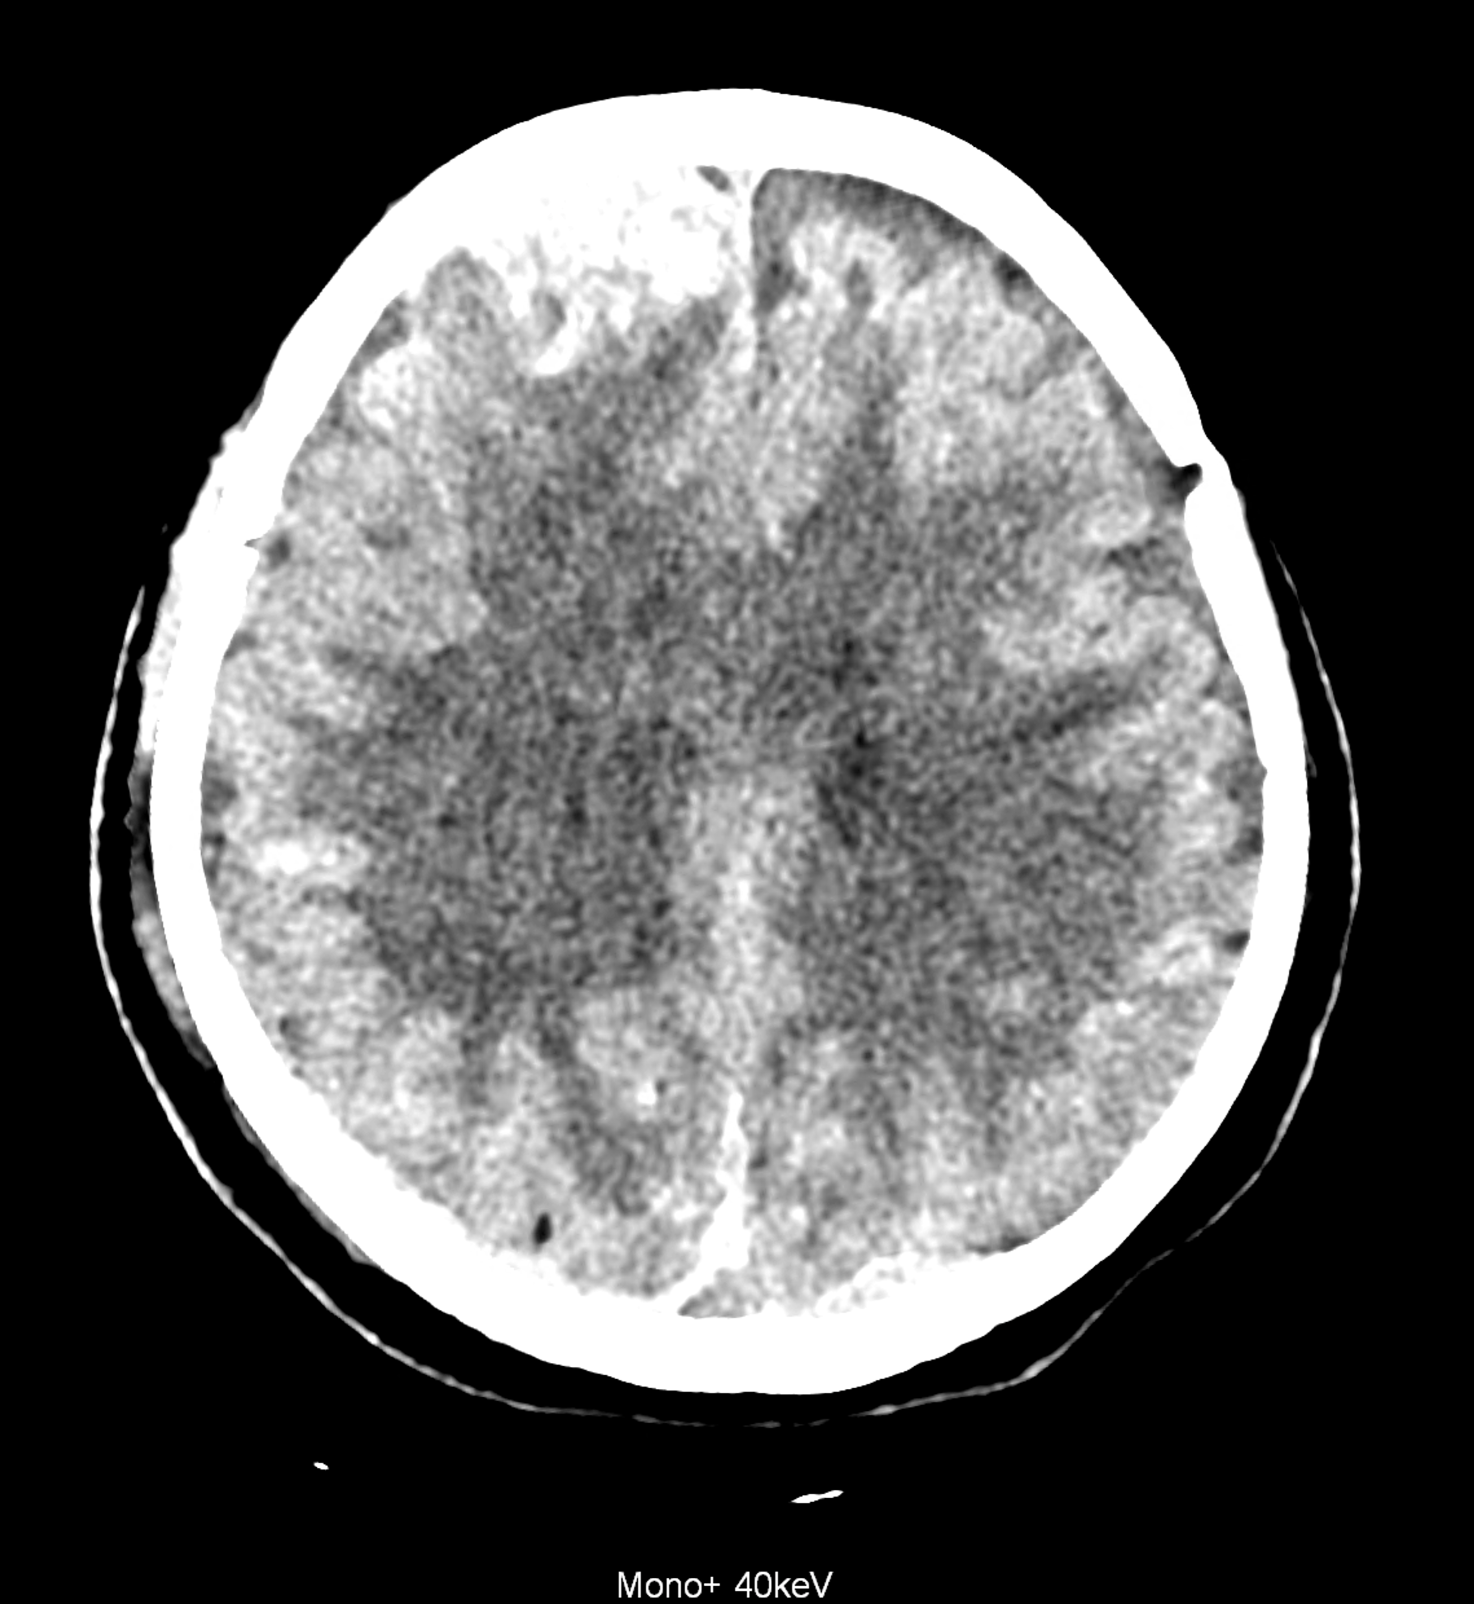

Bleeding is characterized by different absorption characteristics than healthy brain tissue (both gray and white matter) and cerebrospinal fluid. Due to the higher proportion of proteins with amino acids with disulfide bonds, the signal intensity increases at higher energies, making it possible to use monoenergetic imaging at energies above 140 keV, and/or virtual non-contrast. The hemorrhage then becomes more hyperdense, while the rest of the brain tissue acquires a uniform low signal. In addition to bleeding, areas of extracellular fluid of vasogenic origin are also imaged, i.e., in areas around contusion-type brain tissue injuries.

An example of the use of spectral imaging in complex brain injury, where contusions, diffuse axonal injury, subarachnoid hemorrhage, subdural hemorrhage, and blood in the ventricular system are present.

comparison of the images with the energies of monoenergetic reconstructions 40 keV, 67 keV (standard conventional reconstruction), 190 keV and virtual non contrast (VNC)